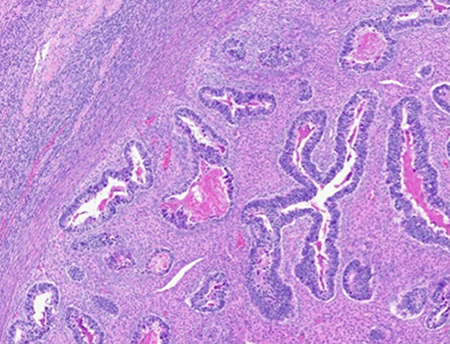

Microscopic examination confirmed carcinosarcoma [figure 3] and revealed heterologous elements, including osteosarcoma and chondrosarcoma [figure 4 and 5]. Metastatic carcinomatous component was identified in the right ovary (1.0 cm) [figure 6], left ovary (0.2 cm), as well as right para-ovarian tissue with tumor cells residing in lymphovascular spaces. The tumor was staged at pathological stage pT3a and a FIGO stage IIIA: local and/or regional spread of the tumor, invading serosa of the corpus uteri and/or adnexa. Finally, the patient was started on adjuvant chemotherapy with carboplatin and paclitaxel.

Figure 3. Medium power view of high-grade malignant stroma surrounding malignant high-grade glandular epithelium arranged in a biphasic pattern.

The stromal component above reflects a homologous undifferentiated sarcoma composed of polymorphous round to spindled cells with large vesicular nuclei, coarse chromatin, scant cytoplasm, and readily identifiable mitotic figures. The epithelial component above demonstrates serous carcinoma, however, can be composed of endometrioid, clear cell, or squamous carcinoma.